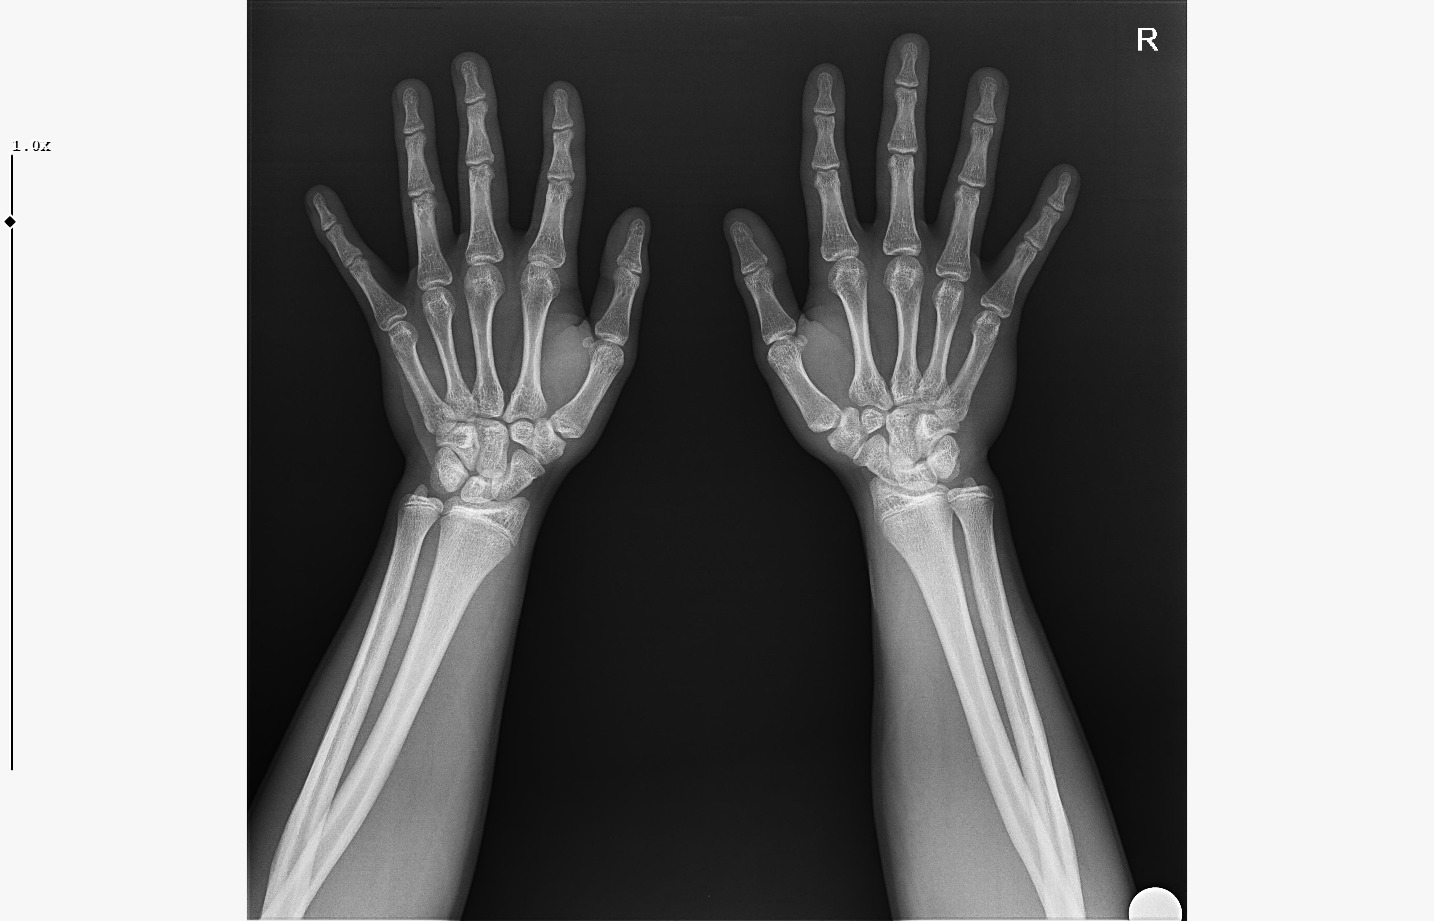

doktor bi sik bilmiyodur büyük ihtimalle plakları buraya at biz bakak

bide bir sekilde hgh temin et babandan kısasın uzama olasılığın çok daha fazla gh ile,şuan ona paran yoksa da biriktirmeye başla aromasin kullan

IMG 5959

röntgeni atar mısın?

böyle ne diyorsun yaşım genc bu arada

Attachments

• WhatsApp Image 2026-01-07 at 00.31.08 (4).jpeg

WhatsApp Image 2026-01-07 at 00.31.08 (4).jpeg

161.8 KB · Views: 0

• WhatsApp Image 2026-01-07 at 00.31.08 (3).jpeg

WhatsApp Image 2026-01-07 at 00.31.08 (3).jpeg

104.8 KB · Views: 0

• WhatsApp Image 2026-01-07 at 00.31.08 (1).jpeg

WhatsApp Image 2026-01-07 at 00.31.08 (1).jpeg

140.5 KB · Views: 0

• WhatsApp Image 2026-01-07 at 00.31.08.jpeg

WhatsApp Image 2026-01-07 at 00.31.08.jpeg

138.6 KB · Views: 0

bilmiyo zaten,ki el plakları boy ile neredeyse hicbirsey göstermiyo bile ama tr de hangi doktora gidersen git %95inden fazlası el plağına bakcak ona göre yorum yapcak

kapanmaya baslamıs ama cok yakın degil

kemik yaşın 15 gibi 15'e çok yakın

anne baba boyun ve yaşını bilmiyorum sadece bu bilgilerle 171-175 arası diye tahmin ediyorum röntgen ile.

normalde anne babana göre 171-176 olman gerek zaten. kemik yaşın ve şuanki boyun ile yapılacak tahmin anne baban ile yapılabilecek tahminle nerdeyse birebir aynı yani büyük ihtimal o civarlar olursun bence